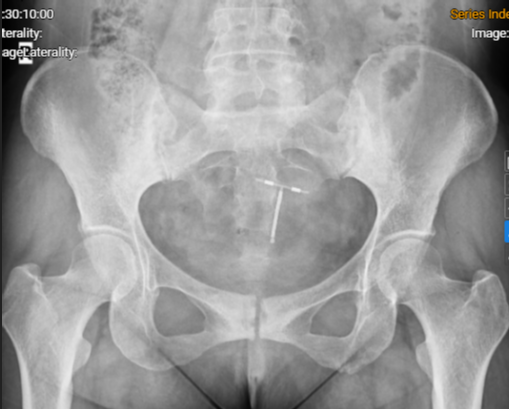

Hình ảnh phim chụp Xquang khớp cùng chậu của người bệnh: Viêm khớp cùng chậu độ III

Người bệnh được chỉ định chụp cộng hưởng từ (MRI) cột sống lưng, cột sống ngực và khớp cùng chậu, xét nghiệm cho thấy người bệnh mang kháng nguyên HLA-B27 dương tính. Người bệnh được chẩn đoán: Viêm cột sống dính khớp, một bệnh tự miễn mạn tính thuộc nhóm bệnh lý cột sống – khớp có thể gây biến dạng, dính khớp, tàn phế nặng nếu không được điều trị kịp thời và đúng cách.